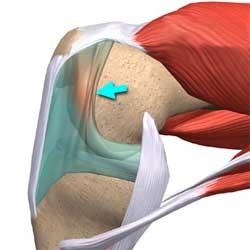

قیمت: 52٬500 تومان - دسته بندی فایل: پاورپوینتدانلود پاورپوینت آسیب acl یا رباط صلیبی قدامی در زانو

خرید پاورپوینت حرفه ای با موضوع آسیب acl یا رباط صلیبی قدامی در زانو از لوکس فایل

قیمت: 52٬500 تومان - دسته بندی فایل: پاورپوینتدانلود پاورپوینت آشنایی با کندرومالاسی پاتلا

خرید پاورپوینت حرفه ای با موضوع آشنایی با کندرومالاسی پاتلا از لوکس فایل

قیمت: 52٬500 تومان - دسته بندی فایل: پاورپوینتدانلود پاورپوینت جراحی استئوتومی زانو

خرید پاورپوینت حرفه ای با موضوع جراحی استئوتومی زانو از لوکس فایل

قیمت: 57٬000 تومان - دسته بندی فایل: پاورپوینتدانلود پاورپوینت جراحی و ایمپلنت زانو

خرید پاورپوینت حرفه ای با موضوع جراحی و ایمپلنت زانو با قیمت استثنایی از لوکس فایل

قیمت: 52٬500 تومان - دسته بندی فایل: پاورپوینتدانلود پاورپوینت آشنایی با کیست بیکر زانو

خرید پاورپوینت حرفه ای با موضوع آشنایی با کیست بیکر زانو با قیمت استثنایی از لوکس فایل

قیمت: 57٬000 تومان - دسته بندی فایل: پاورپوینتدانلود پاورپوینت سندروم پلیکا زانو چیست

خرید پاورپوینت حرفه ای با موضوع سندروم پلیکا زانو چیست با قیمت استثنایی از لوکس فایل

قیمت: 57٬000 تومان - دسته بندی فایل: پاورپوینتدانلود پاورپوینت بررسی عارضه آرتریت پاتلوفمورال

خرید پاورپوینت حرفه ای با موضوع بررسی عارضه آرتریت پاتلوفمورال با قیمت استثنایی از لوکس فایل

قیمت: 52٬500 تومان - دسته بندی فایل: پاورپوینتدانلود پاورپوینت استئوکندریت دیسکان چیست

خرید پاورپوینت حرفه ای با موضوع استئوکندریت دیسکان چیست با قیمت استثنایی از لوکس فایل